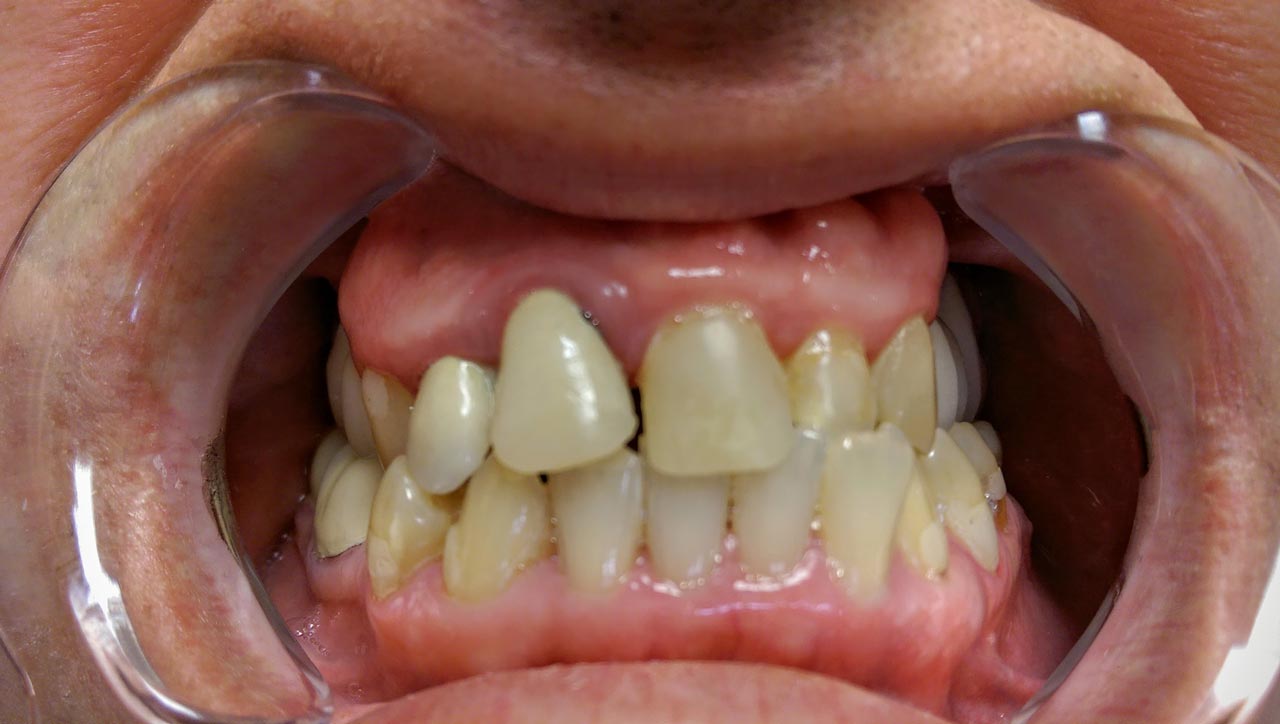

Két eset - előtte és utána

• Páciens #2 - Előtte

Páciens #2 - Előtte

Páciens #2 előtte:

A Páciens régi fémvázas oldalsó hídja, ill. a bal felső 2-es fog többfelszinű, régi tömései láthatóak, ami esztétikailag zavaróak a Páciens számára.